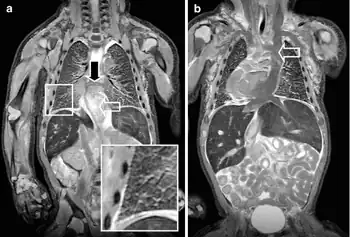

A cyanotic heart defect is any congenital heart defect (CHD) that occurs due to deoxygenated blood bypassing the lungs and entering the systemic circulation, or a mixture of oxygenated and unoxygenated blood entering the systemic circulation. It is caused by structural defects of the heart such as right-to-left or bidirectional shunting, malposition of the great arteries, or any condition which increases pulmonary vascular resistance. The result may be the development of collateral circulation.

- Chest x-ray